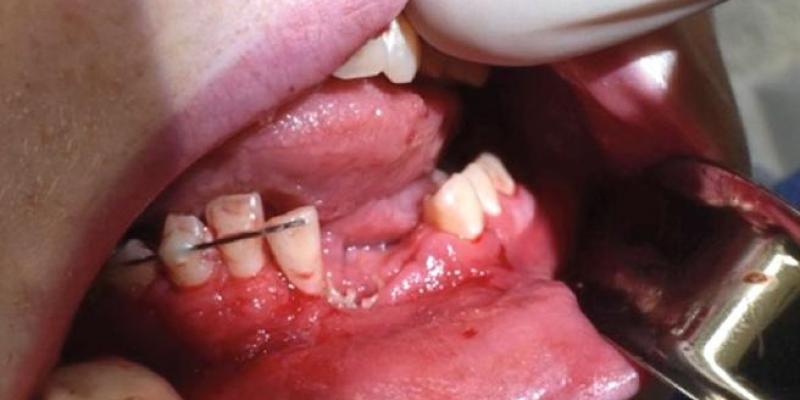

El chico, residente en una pequeña ciudad de Nevada, no presentaba dificultades para respirar aunque sí que tenía la boca destrozada, tanto que hasta perdió parte de la dentadura. También constaba una "punción circular en la barbilla e incongruencia ósea de la mandíbula izquierda”, según explican los médicos Katie Russell y Micah Katz.

Esta incongruencia ósea supone un desencaje en la articulación temporomandibular (ATM), la que existe entre el hueso temporal y la mandíbula, y que impide que el rodamiento sobre el eje sea el adecuado. La afectación puede generar dolores de cabeza, cervicalgias, molestias e incluso pérdida de audición.